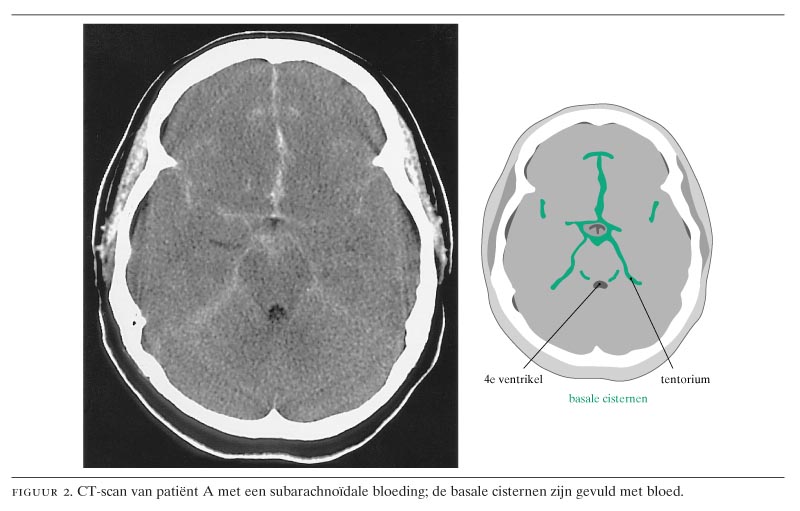

Acute Hevige Hoofdpijn Subarachnoidale Bloeding Nederlands Tijdschrift Voor Geneeskunde